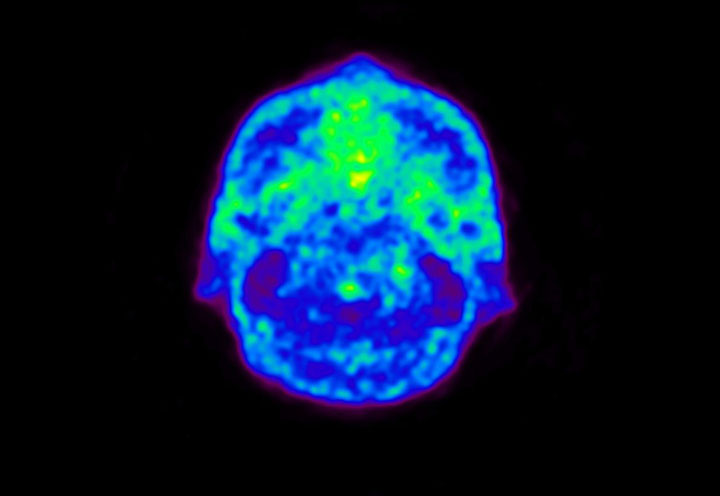

Head / Case5 : Amyloid

Sagittal

Courtesy : Kindai University Hospital

- Imaging protocol

- Injected dose: 4.27 MBq/kg, 18F-Flutemetamol

- Uptake time: 99 minutes

- Scan time: 20 minutes